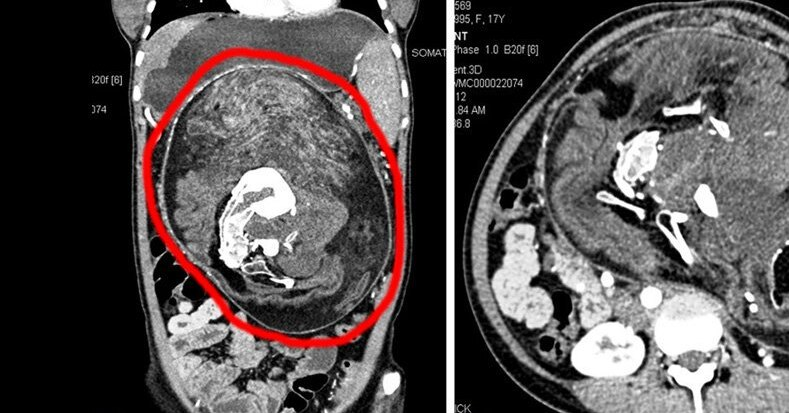

История двухмесячного мальчика из Кабула стала одной из самых громких в 2024 году. Малыш поступил в больницу со вздутием. Ничего необычного, особенно, когда у ребёнка колики в таком возрасте. Однако родители указывали на подозрительно раздутый живот. Первоначально врачи предполагали нефробластому – опухоль почки, часто встречающуюся у младенцев. Однако компьютерная томография показала нечто совершенно иное: в брюшной полости находилось образование, состоящее из мягких тканей, жира, жидкости и костей.

На снимках чётко различались лицевые кости, позвоночник и рёбра – признаки недоразвитого близнеца.

Индия: 17-летний подросток с частями тела брата-близнеца

Самый шокирующий случай последних лет произошёл в Индии. 17-летний юноша жил с частями тела своего неразвившегося близнеца. Из его живота торчали ноги, ягодицы и гениталии – рудименты брата, слившегося с ним ещё в утробе. Паразитирующий близнец весил около 15 килограммов и имел чувствительность к боли и температуре. Несмотря на аномалию, у подростка нормально функционировали кишечник и мочевой пузырь, но он страдал от постоянной боли и проблем с дыханием.

Операция в Индии проходила в несколько этапов. Хирурги разделили сосудистую и нервную сети, которые были общими у обоих организмов, и удалили излишние ткани, включая кисту в брюшной полости. После вмешательства пациент быстро восстановился и уже через несколько дней смог вставать, есть и ходить.